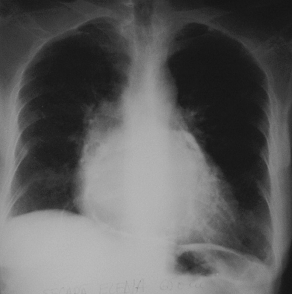

Imagine Rx de pericardita acuta

Semne radiologice cardiopulmonare:

cardiomegalie importanta cu contururi net trasate, stergerea arcuatiei normale, cord 'in carafa',

circulatie pulmonara normala.